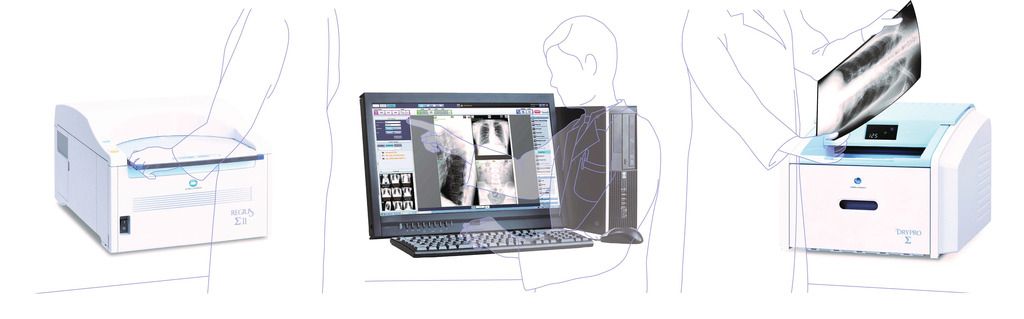

Лазерная камера для печати медицинских изображений на пленке стандарт dicom

/CMI%201000-640x500.jpg)